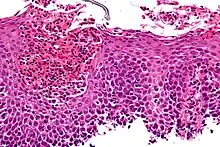

Although it usually assumed that inflammation from acid reflux is caused by the irritant action on the mucosa by hydrochloric acid, one study suggests that the pathogenesis of reflux esophagitis may be cytokine-mediated.[6]

Eosinophilic esophagitis is caused by a high concentration of eosinophils in the esophagus. The presence of eosinophils in the esophagus may be due to an allergen and is often correlated with GERD. The direction of cause and effect between inflammation and acid reflux is poorly established, with recent studies (in 2016) hinting that reflux does not cause inflammation.[6] This esophagitis can be triggered by allergies to food or to inhaled allergens. This type is still poorly understood.

Lymphocytic esophagitis

Lymphocytic esophagitis is a rare and poorly understood entity associated with an increased amount of lymphocytes in the lining of the esophagus.[1] It was first described in 2006. Disease associations may include Crohn's disease, gastroesophageal reflux disease and coeliac disease. It causes similar changes on endoscopy as eosinophilic esophagitis including esophageal rings, narrow-lumen esophagus, and linear furrows.